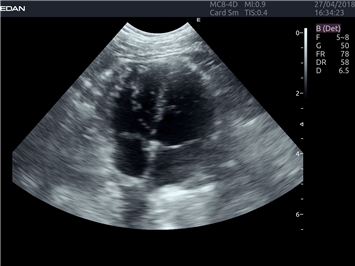

EDAN Acclarix LX4 VET представляет собой профессиональную ультразвуковую систему, специально разработанную для ветеринарных исследований. Сочетание стабильности, высокой производительности и эффективности делает эту систему идеальным выбором для современной ветеринарной практики.

B-режим, Двухмерное сканирование:

Да

Режимы акустической прозрачности 3D: